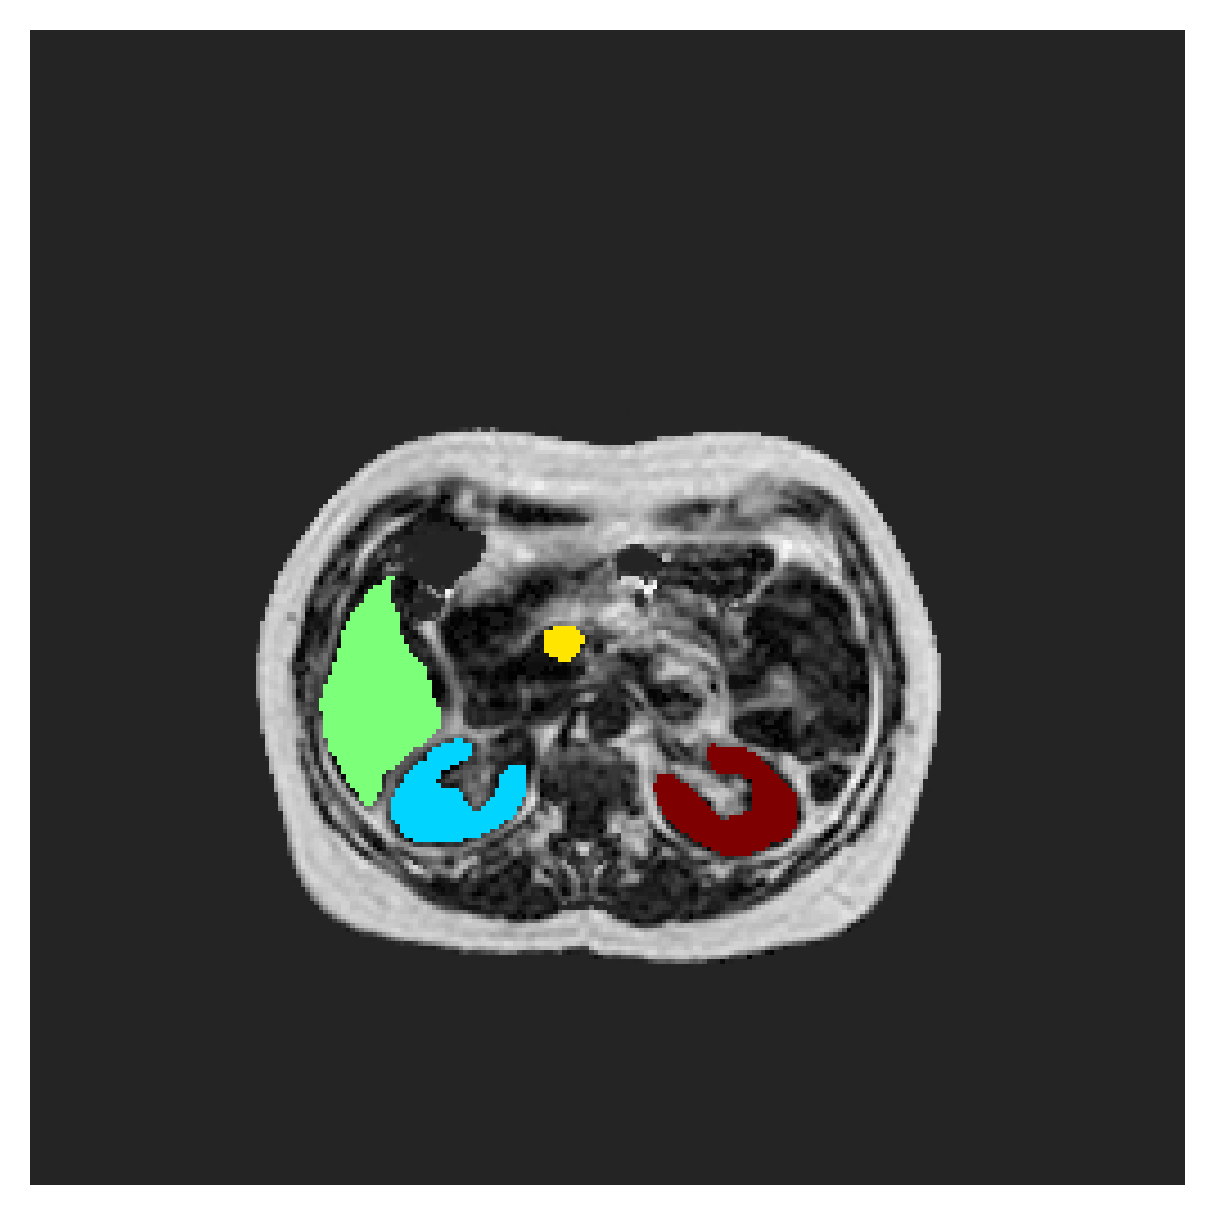

We normalize the volumes and resize the slices to pixels. As the official dataset comes with full annotations, we create a synthetic point ground truth. This is done by first randomly choosing the centers of the point annotations within the class masks, followed by filling an ellipse with axes lengths of and (in pixels) around each center. The intersections of these elliptic discs with the underlying full annotations are then used as our point ground truth. See Figure 2 for an example of the created weak annotation mask. The point annotations are created for every slice, one for each foreground object present in the slice.

The images contain two channels, one for water and one for fat content. For training, we normalize the volumes (per channel) and use 2D slices in the coronal plane, sized . The weak annotations are created synthetically, following the same procedure as described for the ACDC dataset.